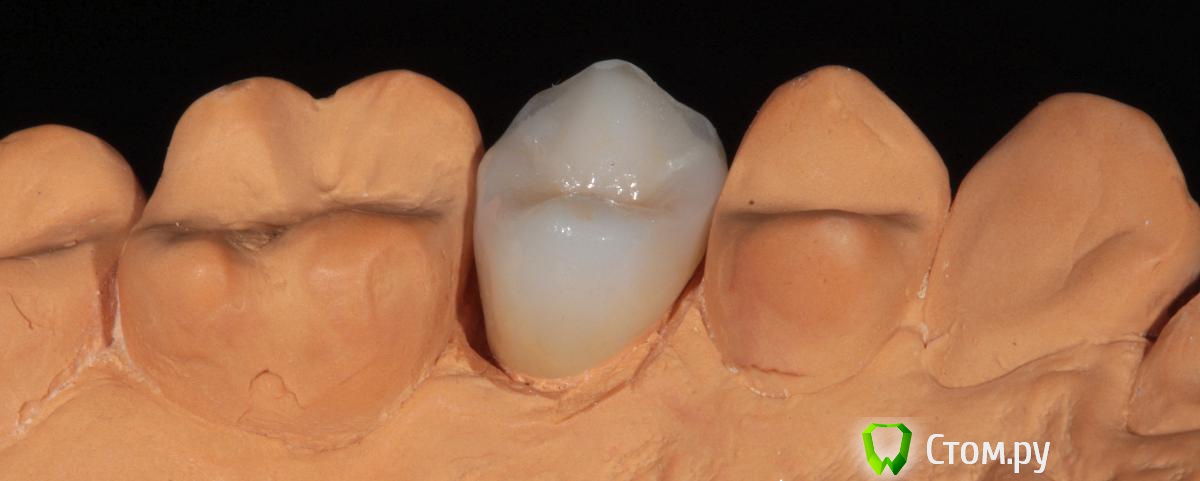

SDC Опубликовано 19 ноября, 2014 Поделиться Опубликовано 19 ноября, 2014 (изменено) Prettau, извините, не знаю, как редактировать название темы. Здравствуйте всем. В хирургическом много практиков, а по протетике - много теории)). Итак, разбавляю вино. (теория вечна)Протезирование премоляров коронками Преттау с нанесением керамики вестибулярно.Много фото, прошу прощения, поэтому без радикала, превью. Наверное даже так лучше, потому, что по клику откроются не сжатые фото, а радикал жмет.Протезирование в течение 2 недель. Фиксация на фуджи, без коффердама, но в сухих условиях (коффер не поставить по причине глубокий дистальной границы препарирования на обоих премолярах - глубокий кариес проксимальных поверхностей в анамнезе)Рг-контроль на предмет остатков цемента и на последнем фото удаленные излишки цемента на перчатке. Изменено 19 ноября, 2014 пользователем SDC 7 Ссылка на комментарий

SDC Опубликовано 20 ноября, 2014 Автор Поделиться Опубликовано 20 ноября, 2014 Отличный результат. Позвольте несколько вопросов.СВШ в боковых не ставите вообще,если да,то по какой причине?Как думаете антагонисты не будут истираться?Вы как-то меняете анатомию контакта при глубоких дефектах и недостатка сосочка?Спасибо.Спасибо Роман.По поводу штифтов. На самом деле, не имеет значения для меня.Важно, что не было титановых во фронтальном отделе (открываются при редукции тв.тк. небольшой объем композита вокруг штифта, что приводит к хрупкости билдапа и иногда металл.штифты светят через композит и керамику)Антагонисты истираться будут, а цирконий - нет. Что поделаешь.Сейчас мы с техником делаем нанесение вестибулярно и по скатам бугров, для уменьшения негативного эффекта повышенной прочности циркония и ускорения сдаваемости.контакт всегда площадочный, пятно контакта в корональной 1/4.Дефицит мягких тканей керамикой никогда не восполняем. Моделировка коронки максимально анатомична. Ссылка на комментарий